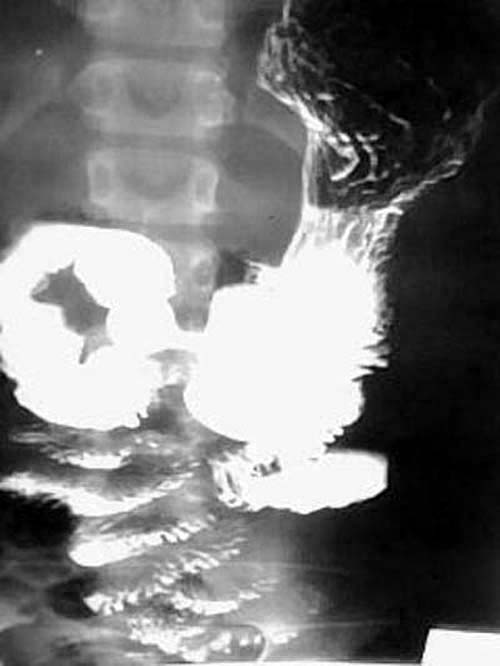

女性,12岁,因腹痛,恶心呕吐一周,腹呈绞痛,痛时可扪及包块,呕吐物为胆汁.大便不成形.于外院输液无好转(具体不详),遂转入我院,经对症治疗3天后好转,

服钡后两小时半摄片:

ped0661结果:中肠旋转不良伴中肠扭转.为手术所证实

本例是典型的中肠旋转不良伴中肠扭转的病例.为手术所证实.

本例临床表现是上消化道梗阻的表现.但初入院时外科诊断并不明确.透视未见明显异常(其他医生作的,具体不详),两次超声均未能明确诊断.入院后行禁食,胃肠减压,对症,输液等处理,约3天后腹痛缓解.拔胃管的当天吃了二个小包子,第二天作钡餐,钡餐示:十二指肠水平段不全梗阻(腹膜带压迫),空肠在左上腹小段盘曲后随即转向右,并于中腹部呈螺旋形下降(这是中肠旋转不良伴中肠扭转的典型表现),大部份回肠位于左下腹.因外科开的是上消化道钡餐,我已经把大部份小肠都看了,又到了下班时间,就没有继续往下追踪,如果断续追踪发现盲肠的位置异常,则可进一步的证实和肯定诊断.

中肠的旋转不良合并扭转在术前是可以确诊的,肠旋转不良作钡餐时不时可以见到,但合并扭转的并不多。根据本人体会及结合文献,中肠的旋转不良合并扭转,可以没有肠梗阻,但也可以有梗阻,甚至绞窄,坏死。几年前我也遇见过一位成人的小肠旋转不良伴扭转的病例.患者大约四、五十岁.没有明显肠梗阻,(遗憾的是胶片已销毁,不然可请老师们鉴别一下)。但不论有无梗阻,一旦发现有扭转均为手术指征。

钡餐检查可获得肠旋转不良的全部信息,包括十二指肠有无梗阻、十二指肠空肠曲位置、有无肠扭转及回盲部位置,是诊断本病的首选方法。钡灌肠造影发现回盲部在左腹部或右上腹部,可确诊肠旋转不良,但不能诊断是否并发中肠扭转。